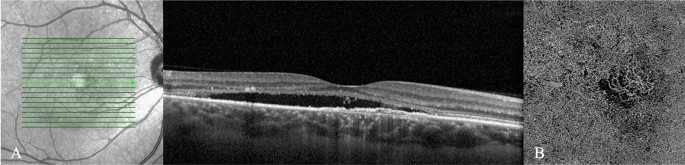

Binomial logistic regression was performed to ascertain the effects of these factors on the likelihood that participants have pMNV rather than neovascular MNV (Table 3). The logistic regression model resulted statistically significant (χ2 = 71.65, p < 0.001). The B coefficient of each significant predictive factor was considered as a whole number, disregarding the decimal places. The numbers so obtained for all factors were assumed as the points contributing to the final simplified predictive score. Age (+ 2 points), sex (+ 2 points), choroidal thickness (+ 2 points), early pachyvessels (+ 2 points, Fig. 1), and evidence of MNV at OCTA (+ 3 points, Fig. 2) were factors associated with an increased likelihood of exhibiting pMNV. Four extra factors significant at univariate analysis but non-significant at logistic regression were integrated in the scoring system. Most specifically, type 2 and type 3 MNVs, and the presence of IF were assumed to give − 0.5 points each, whereas the presence of SRF was assumed to give + 0.5 points. InCASEOf scoring system was built based on these results with a high score of 11.5 points (Table 4).

(A) Enhanced-depth imaging optical coherence tomography reveals dilated Haller’s layer vessels and attenuation of the choriocapillaris, and a flat irregular pigment epithelium detachment (FIPED) associated with subretinal fluid (SRF) and subretinal hyperreflective foci. (B) The enface OCT angiography demonstrates a neovascular lesion with tangled filamentous pattern within the FIPED.